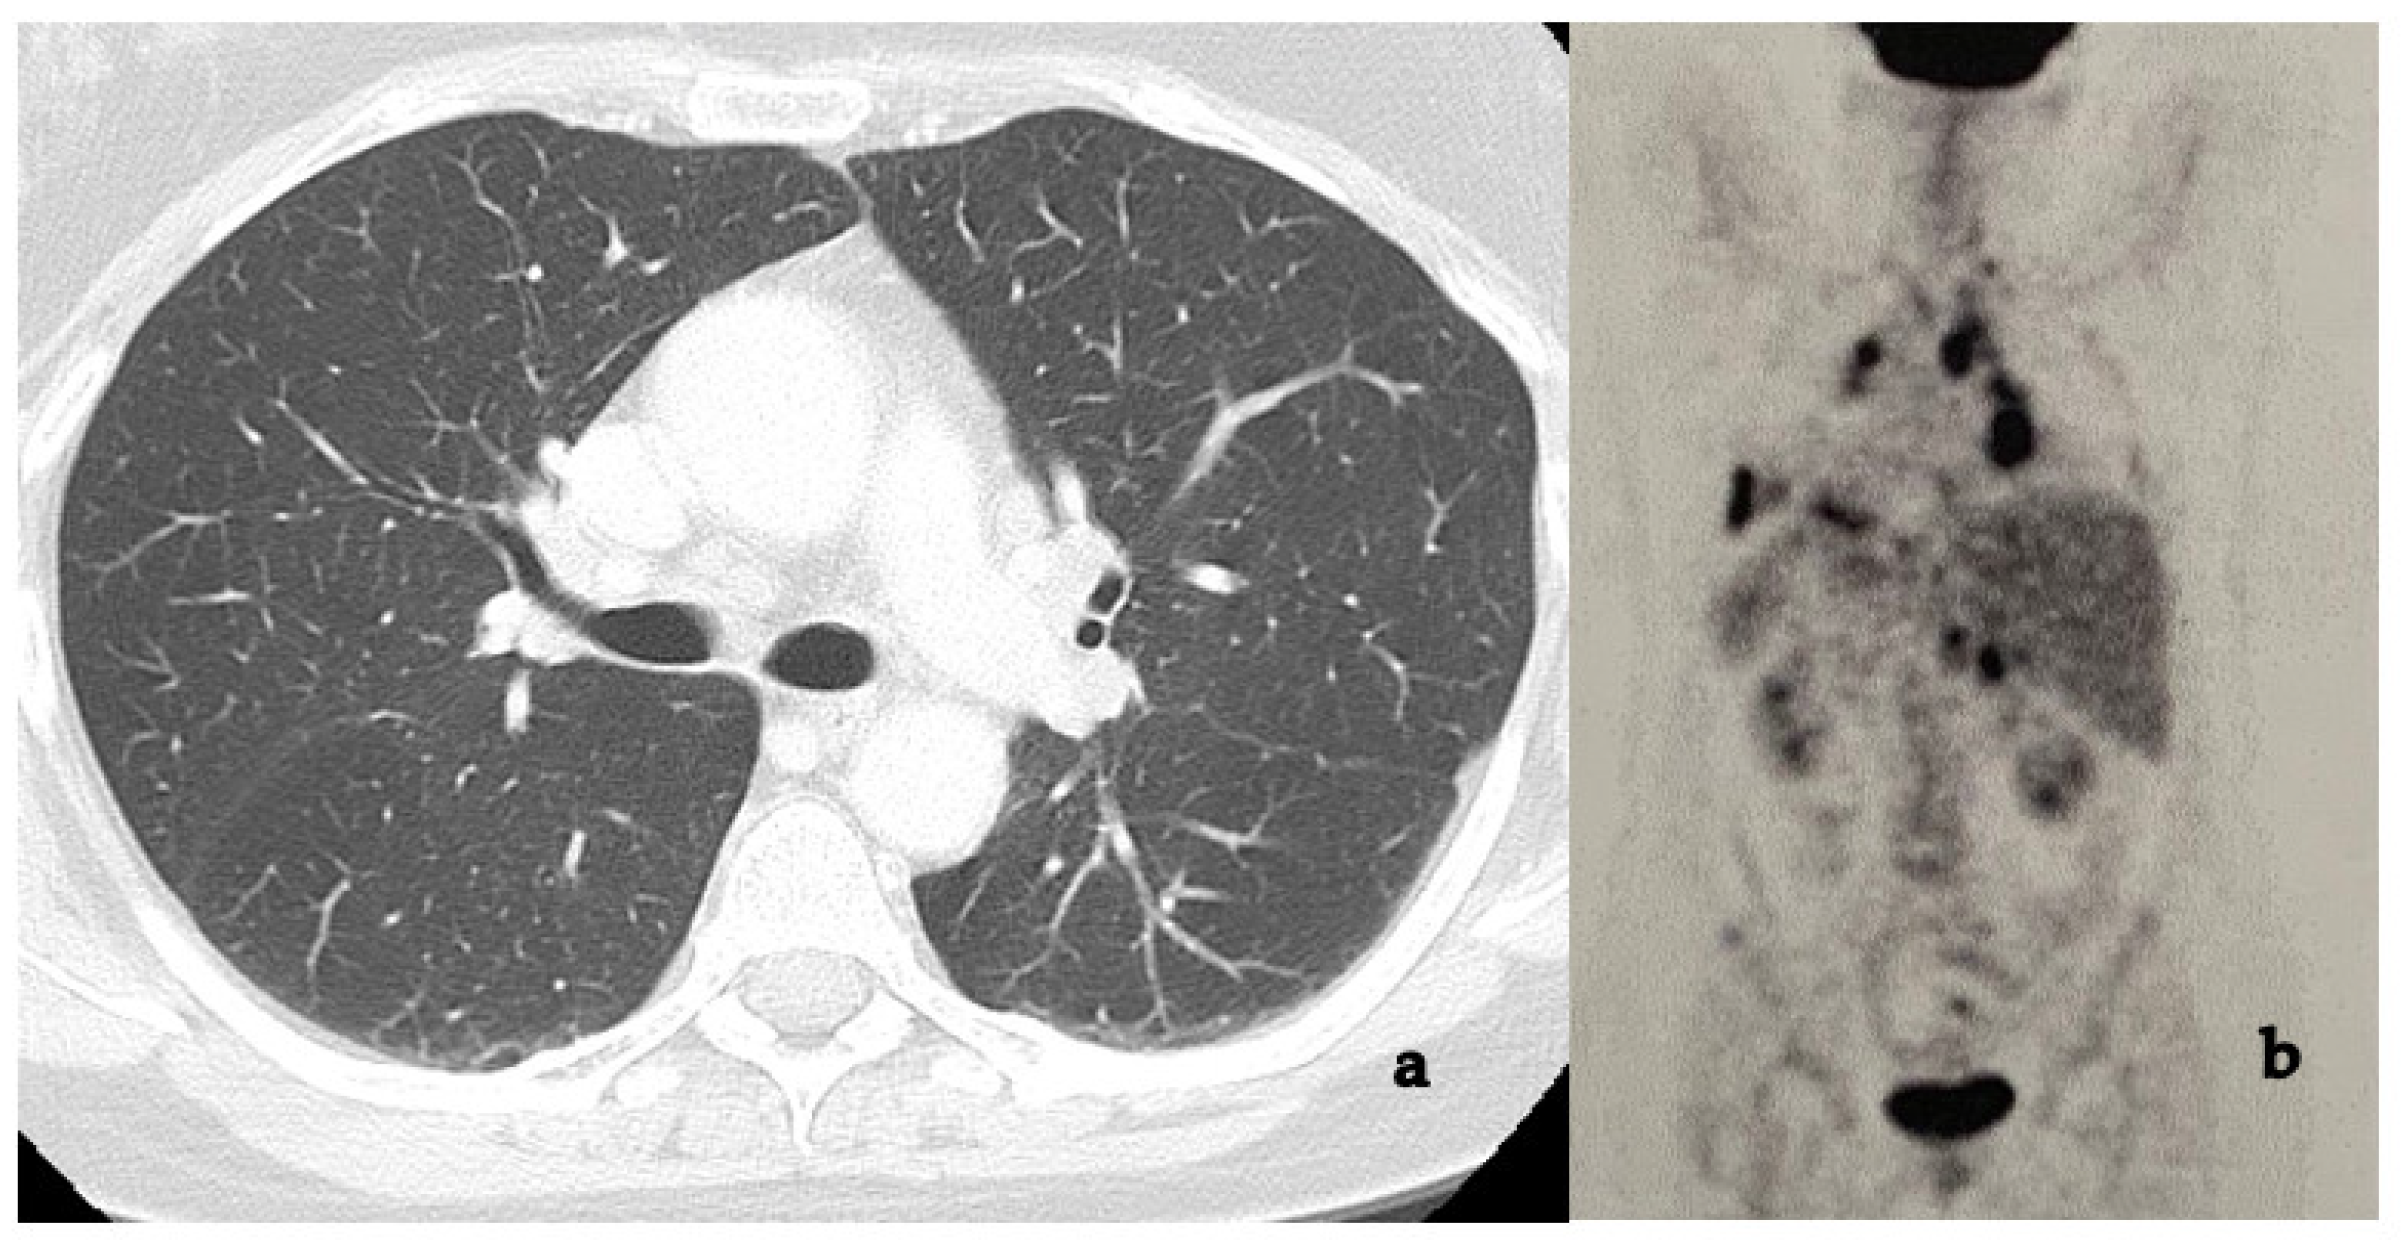

- Vagal, A.S.; Shipley, R.; Meyer, C.A. Radiological manifestations of sarcoidosis. Clin. Dermatol. 2007, 25, 312–325. [Google Scholar] [CrossRef]

- Ors, F.; Gumus, S.; Aydogan, M. HRCT findings of pulmonary sarcoidosis; Relation to pulmonary function tests. Multidiscip. Respir. Med. 2013, 8, 8. [Google Scholar] [CrossRef]

- Kaiser, P.K.; Lowder, C.Y.; Sullivan, P.; Sanislo, S.R.; Kosmorsky, G.S. Chest computerized tomography in the evaluation of uveitis in elderly women. Am. J. Ophthalmol. 2002, 133, 499–505. [Google Scholar] [CrossRef]

- Clement, D.S.; Postma, G.; Rothova, A.; Grutters, J.C.; Prokop, M.; de Jong, P.A. Intraocular sarcoidosis: Association of clinical characteristics of uveitis with positive chest high-resolution computed tomography findings. Br. J. Ophthalmol. 2010, 94, 219–222. [Google Scholar] [CrossRef] [PubMed]

- Ganesh, S.K.; Roopleen, B.J.; Veena, N. Role of High-resolution Computerized Tomography (HRCT) of the chest in granulomatous uveitis: A tertiary uveitis clinic experience from India. Ocul. Immunol. Inflamm. 2011, 19, 51–57. [Google Scholar] [CrossRef]

- Mehta, S. Observed Patterns of Systemic Disease on PET/CT scan in patients with presumed ocular tuberculosis: Findings and hypotheses. Ocul. Immunol. Inflamm. 2018, 26, 217–219. [Google Scholar] [CrossRef]

- Sève, P.; Billotey, C.; Janier, M.; Grange, J.D.; Broussolle, C.; Kodjikian, L. Fluorodeoxyglucose positron emission tomography for the diagnosis of sarcoidosis in patients with unexplained chronic uveitis. Ocul. Immunol. Inflamm. 2009, 17, 179–184. [Google Scholar] [CrossRef]

- Rahmi, A.; Deshayes, E.; Maucort-Boulch, D.; Varron, L. Intraocular sarcoidosis: Association of clinical characteristics of uveitis with findings from 18F-labelled fluorodeoxyglucose positron emission tomography. Br. J. Ophthalmol. 2012, 96, 99–103. [Google Scholar] [CrossRef]

| Chest HRCT Findings | No. | % |

| Patients | 215 | 91.5 |

| Hilar and/or Mediastinic Lymphadenopathy | 142 | 60.4 |

| Parenchimal involvement | 94 | 40 |

| Combination | 31 | 13.2 |

| Negative | 16 | 6.8 |